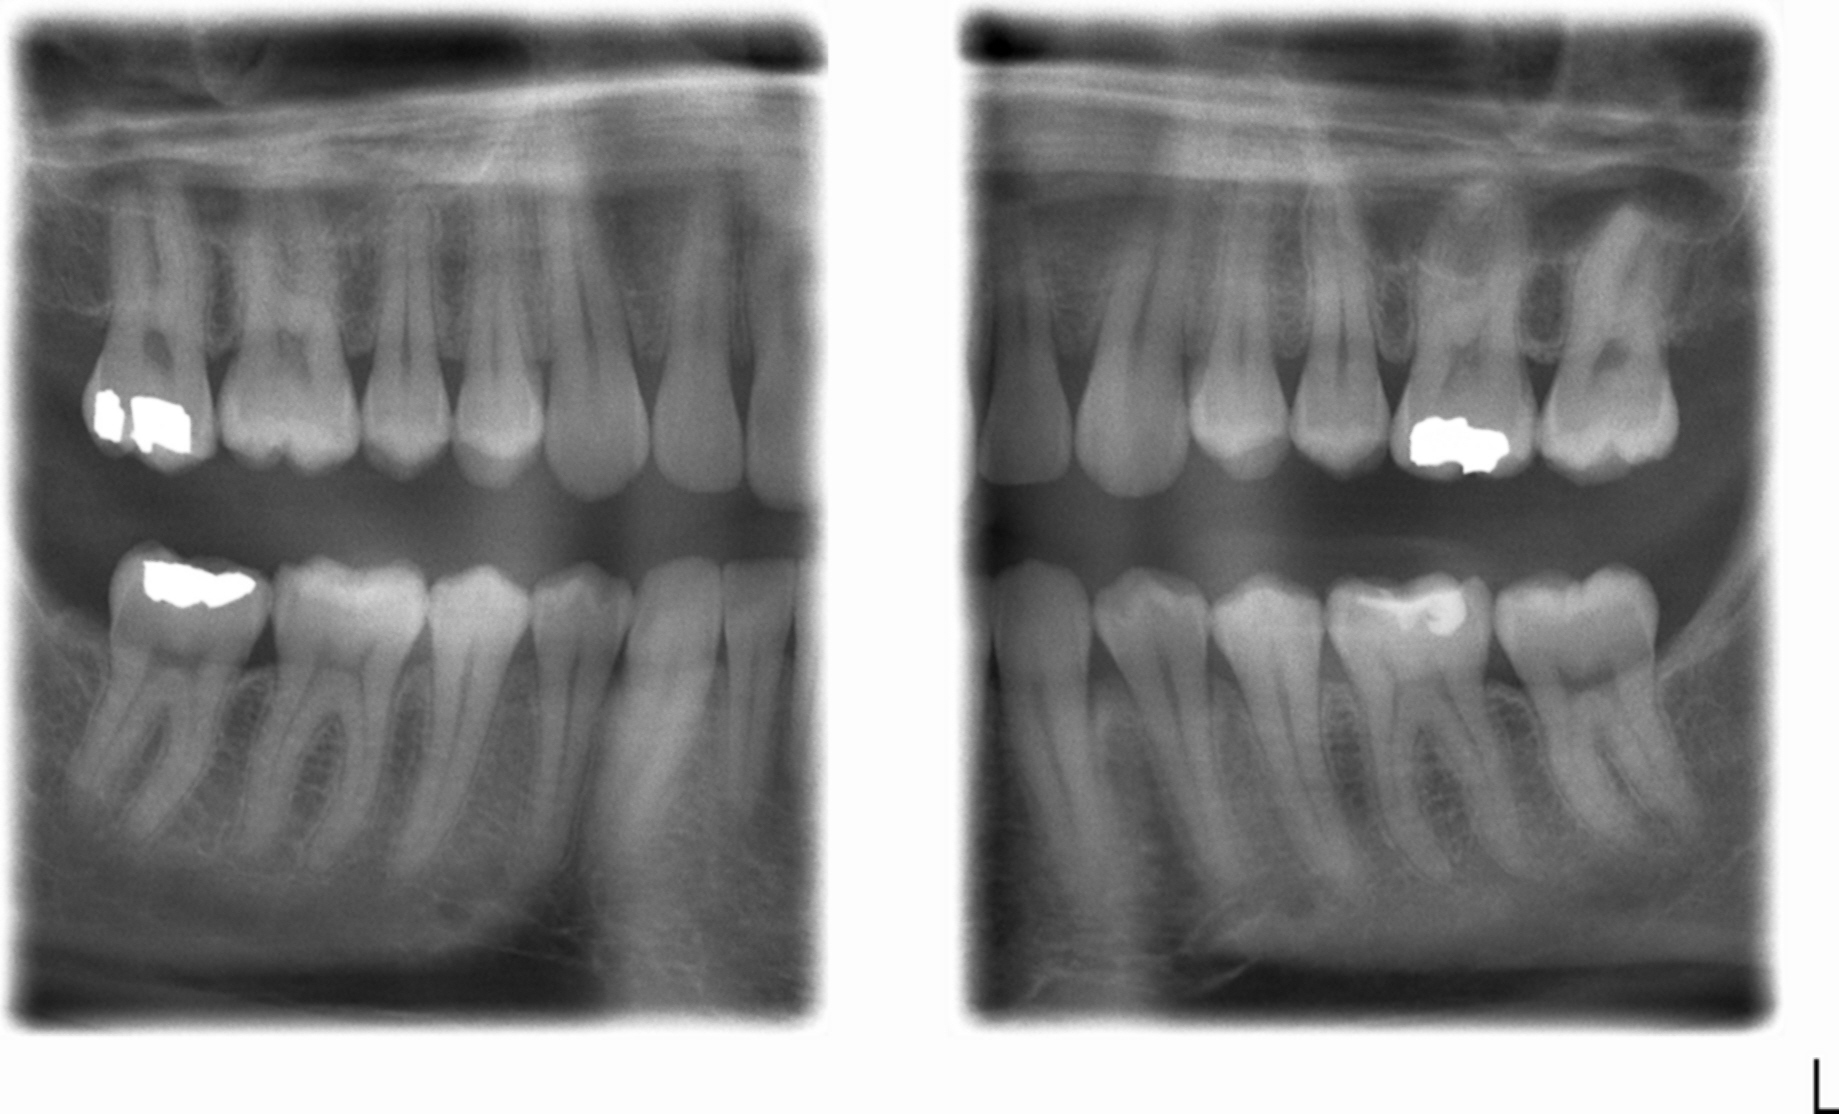

The image displays the crown of your top and bottom teeth. Bitewing radiograph is still the most reliable and widely used method in clinical situations. Objectives to identify guidelines on when and how frequently bitewing radiographs should be used in dentistry for the diagnosis of caries, and to. Bitewings involve two to four individual films usually taken of the molars. •you're experiencing some kind of tooth pain or discomfort.

Samples of bitewing radiographs showing groundtruth manual annotations Bitewing X Ray Cancer •you're experiencing some kind of tooth pain or discomfort. Bitewings involve two to four individual films usually taken of the molars. Objectives to identify guidelines on when and how frequently bitewing radiographs should be used in dentistry for the diagnosis of caries, and to. The image displays the crown of your top and bottom teeth. Bitewing radiograph is still the. Bitewing X Ray Cancer.